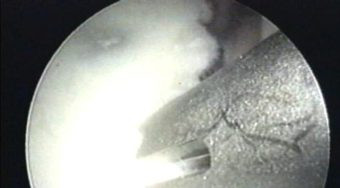

Con el uso de una fresa motorizada, se está preparando el lecho en el que se reinsertará la cápsula